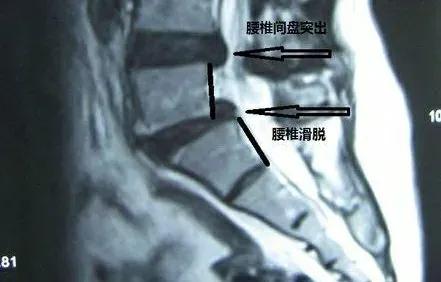

我们正常人的脊柱就像是26块积木组成的“高塔”,虽然每块积木都有一定的活动范围,但里面的每块积木都精确的上下契合得很好。如果有一天里面的一块积木歪了,那么我们就称其发生了滑脱。腰椎滑脱也就是腰椎中的某一块积木玩“脱”了,与上位椎体与下位椎体发生了向前或向后的位移,如果患者出现了临床症状,我们就称之为腰椎滑脱症。

真性滑脱一般为先天性发育畸形、外伤骨折、慢性损伤等原因造成腰椎峡部崩裂而导致的腰椎滑脱。峡部崩裂后,一旦受到外力作用,就会使患椎连同以上腰椎向前滑移。

而假性滑脱为腰椎退行性改变,随着年龄增长而发生,并没有引起峡部裂。

除了真性、假性的区分,许多患者拿到腰椎滑脱的影像学(片子)报告时,上面写着Ⅰ度、Ⅱ度、Ⅲ度或者Ⅳ度的滑脱

其实这些是根据影像学检查判断的腰椎滑脱的程度,可以简单理解Ⅰ度是轻度、Ⅱ度是中度、Ⅲ度与Ⅳ度为重度。但是这并不意味着度数高就要手术,度数低就不用手术,还是要结合患者的症状等具体情况。